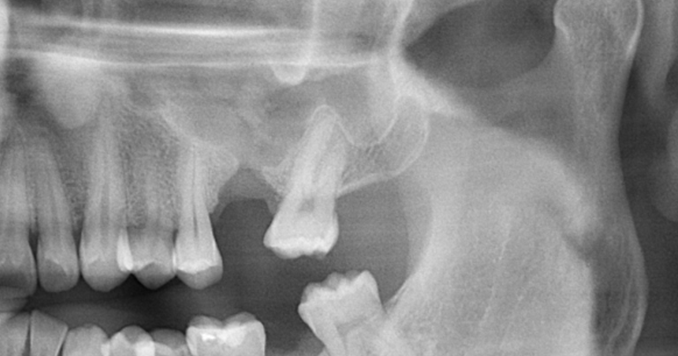

COMUNICACIÓN BUCOSINUSAL

Subtopic